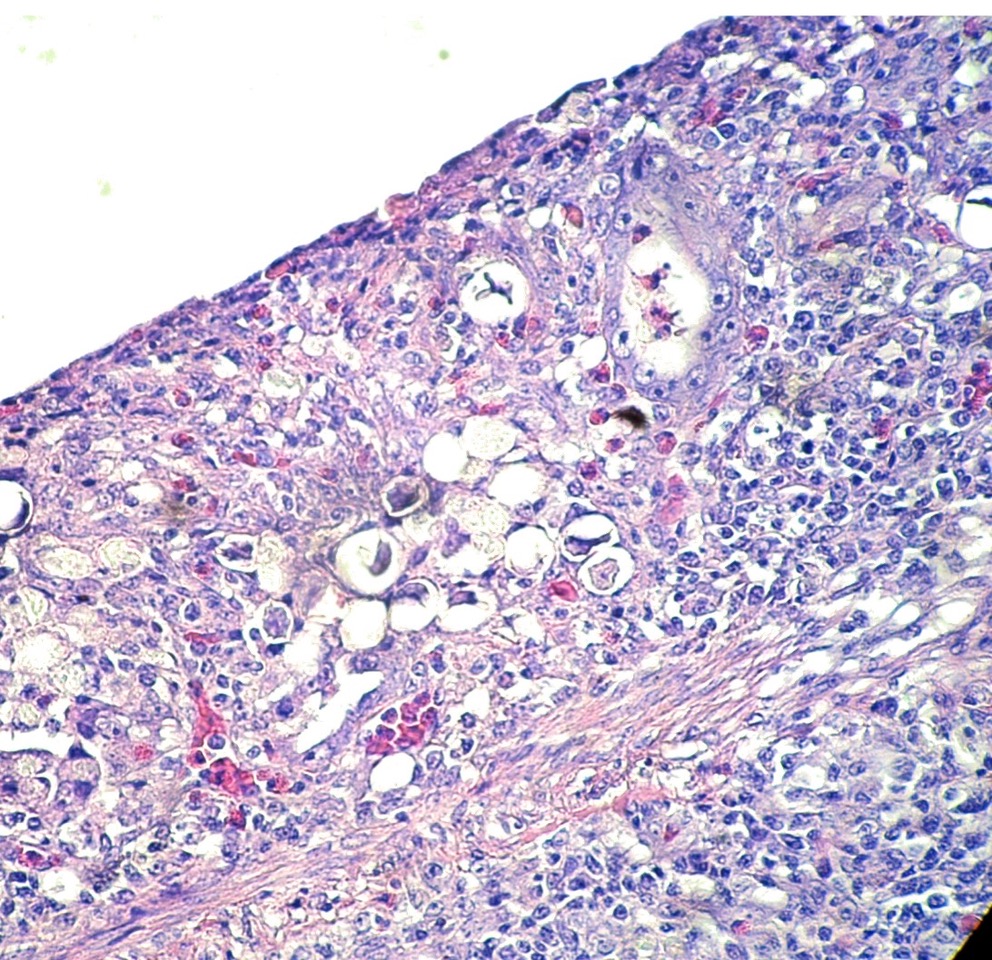

Coupe histologique x40 HE Coccidiose

Dans le cas de la coccidiose, il est fréquent de voir du sang dans les fientes, une diarrhée sévère, une déshydratation et une mortalité élevée chez les jeunes poules.